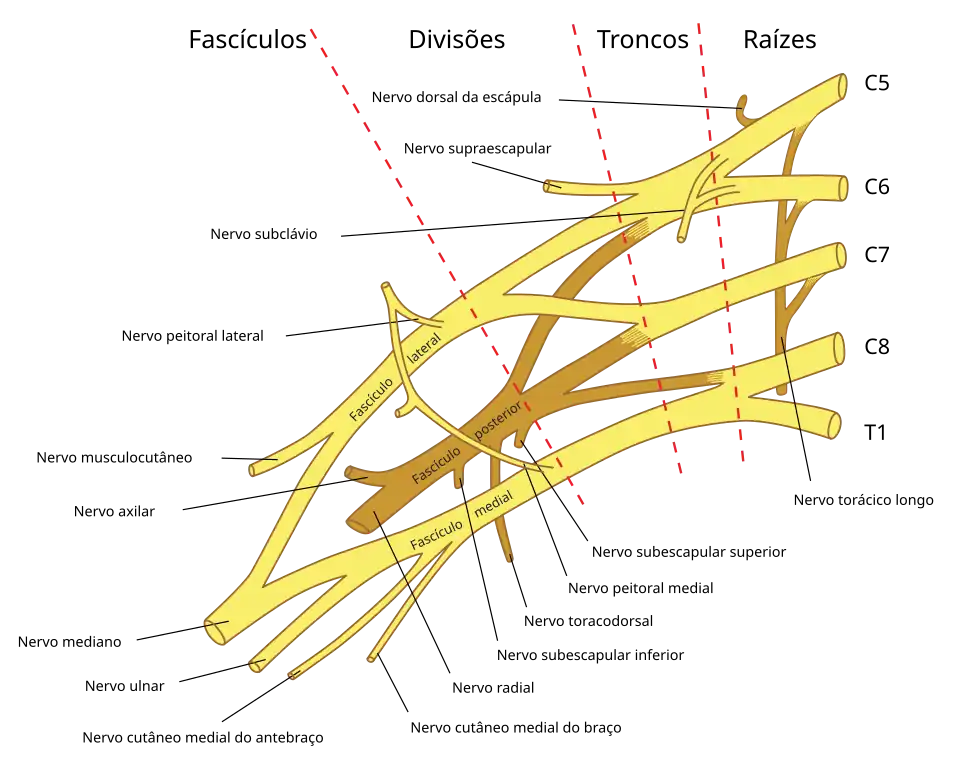

O nervo frênico se origina do 4º nervo cervical, (C4), com contribuições do 3º e 5º nervos cervicais (C3 e C5).[1] Assim, o nervo frênico recebe inervação das partes de ambos o plexo cervical e o plexo braquial.

A contribuição do 5º nervo cervical pode vir a partir de um nervo frênico acessório. O nervo frênico perto da sua origem, é um ramo de comunicação para raiz C5 do plexo braquial. O nervo frênico, no nível da raiz do pescoço, pouco antes de entrar no tórax, fica a frente da veia subclávia. Normalmente, é colocado de forma posterior, entre a veia e a artéria subclávia.[3]

Na maioria das vezes é um ramo do nervo para a subclávia e pode conter várias fibras nervosas frênicas. Se o nervo frênico acessório está presente, encontra-se na lateral do principal nervo e desce posterior e, ocasionalmente, de inferior para a veia subclávia. O acessório do nervo frênico se conecta ao nervo frênico no tórax ou na raiz do pescoço.[1] Em caninos, o nervo frênico surge a partir de C5-C7 com algumas pequena contribuições de C4.[4] Em gatos, cavalos, bois e de pequenos ruminantes, o nervo frênico surge de forma variável a partir de C4-C7.

Lesões do plexo braquial podem causar paralisia para várias regiões do braço, antebraço e mão, dependendo dos nervos cortados. A paralisia resultante tem sido tratada clinicamente, usando o nervo frênico como um doador para neurotização do nervo musculocutâneo e o nervo mediano.[9] Este tratamento tem uma alta taxa de sucesso (84.6%) com restauração parcial a completa da inervação do nervo lesado.[9] Além disso, este procedimento resulta em restituição dos nervos do plexo braquial com o mínimo de impacto para a função respiratória do nervo frênico. As instâncias onde a capacidade vital pulmonar é reduzida têm sido tipicamente um resultado do uso do frênico direito como o doador para a neurotização enquanto que o uso do nervo frênico esquerdo não foi significativamente associado à redução da capacidade vital pulmonar.[10]

O direito do plexo braquial com seus ramos curtos, visto de frente.

O direito do plexo braquial com seus ramos curtos, visto de frente.